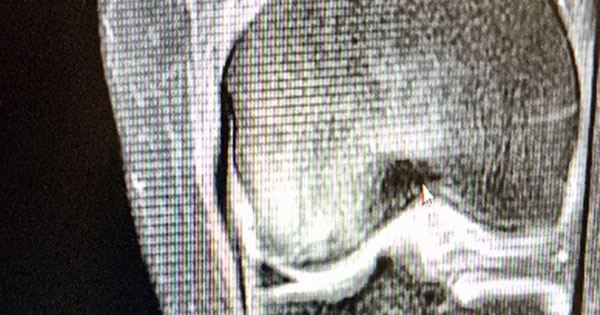

Οστικό Οίδημα – Τι είναι και πώς θεραπεύεται;

Με τον όρο οστικό οίδημα αναφερόμαστε στη μεταβολή του μαγνητικού σήματος στα οστά που απεικονίζεται στην μαγνητική τομογραφία.

Η κλινική αυτή οντότητα περιγράφηκε για πρώτη φορά 1988 από τον Von Wilson όταν η χρήση του μαγνητικού τομογράφου άρχισε να επικρατεί στην διερεύνηση των μυοσκελετικών παθήσεων. Αρχικά η πάθηση αυτή είχε χαρακτηριστεί ως παροδική οστεοπόρωση.